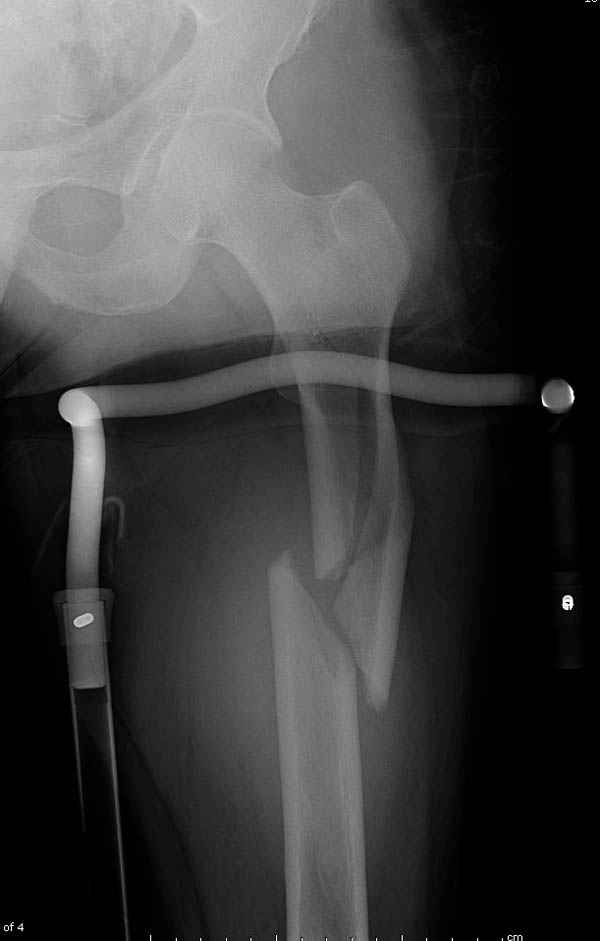

Больному 42, гемофилия типа А, из истории упал с высоты около 1,5 метра, переправлен из другой больницы. По происхождению мексиканец, 10 лет назад по поводу артроза пр. коленного сустава в Мексике сделано протезирование, которое  закончилось ампутацией выше коленного сустава.

При поступлении бедро напряженное, сосудистых и неврологических расстройств нет. На рентгенограмме оскольчатый перелом бедра с вовлечением проксимальной спирали в шейку бедра.

Имя     : 1 injury ap.jpg

Тип     : image/jpeg

Размер  : 26616 байтов

Url     : http://weborto.net:8080/pipermail/ortho/attachments/20090531/91bb3dda/attachment-0003.jpg